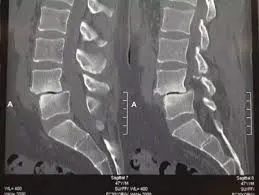

來源:網路

腰椎滑脫是必須經過X-ray的醫學影像判讀的。